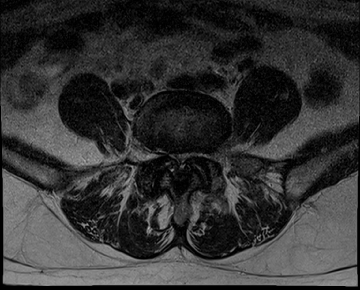

요추 협착증 수술 전·후

2020.08.30

2022.09.06

ㆍ환자 동의를 받은 자료이며, 이미지 사진은 실물과 다를 수 있습니다.

ㆍ모든 자료는 새움병원 자료입니다.